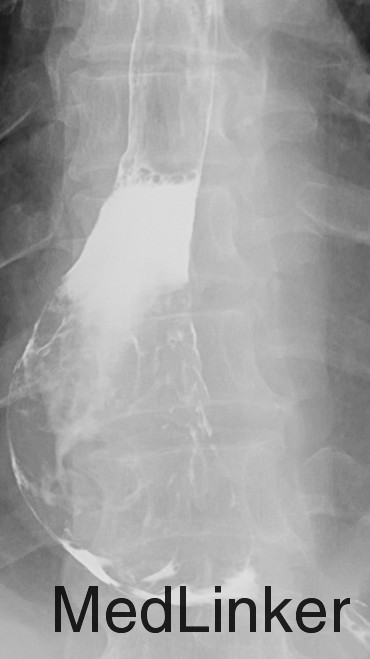

主诉:胸骨后隐痛40天,伴嗳气10天。 现病史:患者40天前无明显诱因出现胸骨后隐痛,呈间断性,无明显加重缓解因素,无放射痛。无进食哽噎感,无吞咽困难,无发热咳嗽,无胸闷心悸,无腹痛腹胀,无头晕头痛。10天前开始,患者出现嗳气不适,胸骨后疼痛无明显加重。于奈曼旗人民医院就诊,查纤维胃镜示“食管占位”。今为求进一步治疗,来我院就诊,门诊以“食管占位”为诊断收入院。患者病来一般状态好,小便正常,大便次数少,腹泻、便秘交替,饮食睡眠好,近期体重减轻约8KG。 。 既往史:否认高血压、冠心病、糖尿病等疾病史;否认肝炎结核等传染病病史;4年前颌面部外伤,否认手术史,否认输血史。否认食物及药物过敏史。预防接种史不详。

查体:T:36.4℃,P:78次/分,Bp:131/77mmHg,R:16次/分。神清语明,步入病房,查体合作,营养状态略差,皮肤粘膜无黄染,结膜无苍白,浅表淋巴结未触及肿大,气管居中,胸廓对称无畸形,呼吸运动正常,双肺叩诊清音,未及明显罗音。心音钝,律齐。腹平软,无压痛及反跳痛,肝脾肋下未触及。肝区叩痛(-),双下肢无水肿,脊柱四肢活动无异常。 辅查:胃镜(奈曼旗人民医院,2015-10-28):食管占位。

诊断 : 食管占位 治疗:入院后完善相关检查,胃镜病理未能予以确定诊断为恶性肿瘤。患者家属拒绝再次胃镜病理检查,要求行手术治疗。 后为解除梗阻症状,提升患者生活质量,按食管恶性肿瘤准备行手术治疗,术中切除肿物并剖开,内部质韧,肿物表面局部溃疡性改变,冰冻回报:平滑肌瘤伴鳞状细胞癌,患者现术后康复中,病理尚未回报。

患者为食管间叶来源肿物恶性,还是食管平滑肌瘤伴发食管癌,希望术后病理能给予进一步解答。